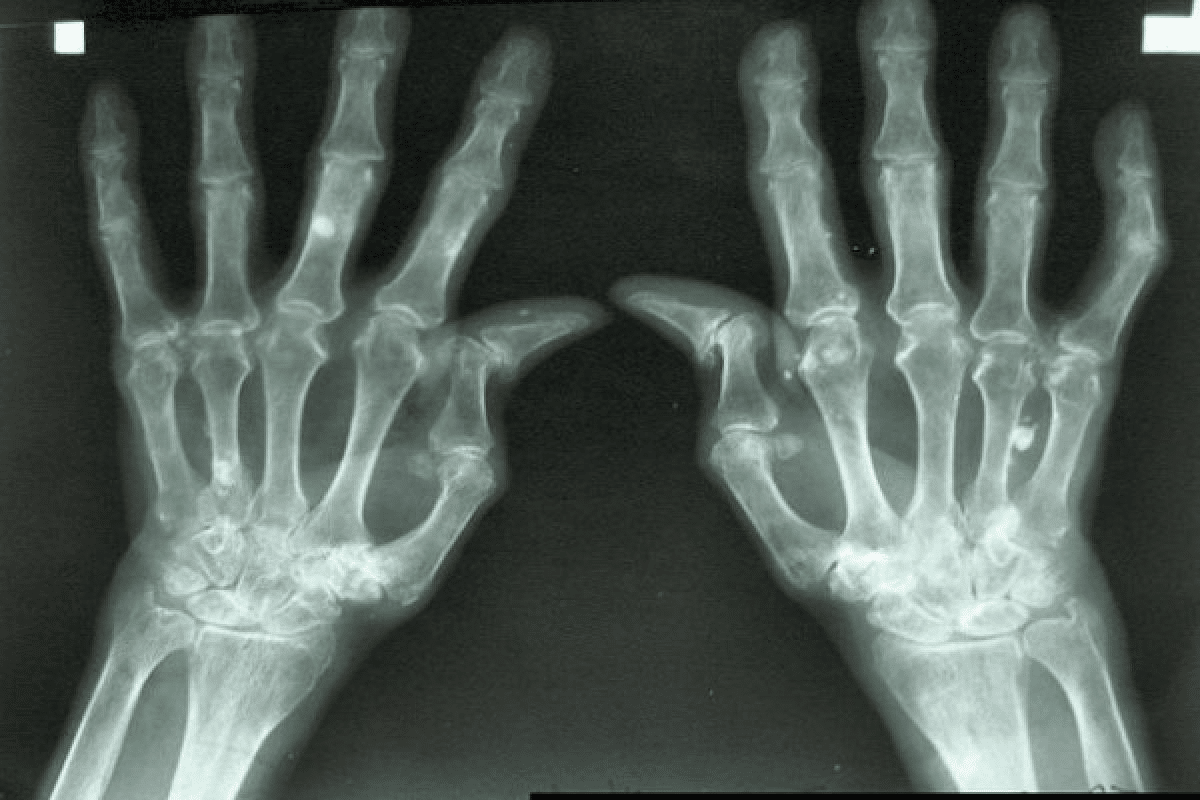

Diagnosing RA in stage 1 is tricky because symptoms are mild and can look like other conditions. X-rays might not show damage yet, making diagnosis hard.

Imaging Techniques: X-rays, MRI, and Ultrasound

Imaging tests are important for checking joint damage and how the disease is progressing.

X-rays

Look at joint damage and bone erosion.